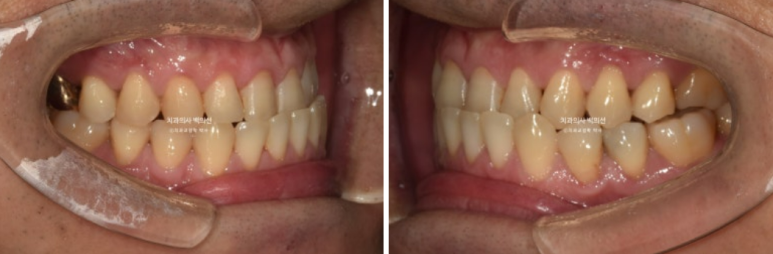

24.10

교정용 나사인 미니스크류를 아래쪽에 2개 심고 3급 고무줄을 걸며 치료를 진행중입니다.

치료시작 10개월차 첫세트의 장치를 모두 낀 후 모습입니다.

큰 공사는 끝났으나 미진한 부분들이 보입니다.

앞니 반대교합은 해결 되었으나 여전히 중심선이 미세하게 안 맞고

어금니 교합이 뜨는 부분이 있어 24년 10월 재제작에 들어갔습니다.

25년 3월까지 4개월동안 추가장치를 모두 낀 후 치료를 마무리 했습니다.